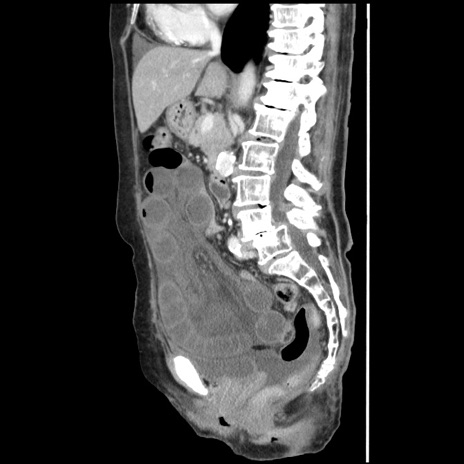

症例1(矢状断像)

【症例】80歳代女性

【主訴】腹痛

【現病歴】8時間前から腹痛あり来院。

【既往歴】糖尿病、脂質異常症、子宮体癌にて子宮全摘術

【身体所見】意識清明・会話良好だが腹痛で苦悶様、全腹部にわたって反跳痛と圧痛あり

【データ】WBC 13600、CRP 0.14、LDH 224、CK 90